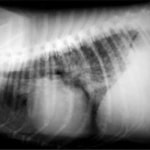

A・B:猫の肥大型心筋症による胸水の貯留 正面像と側面像

C:猫の肥大型心筋症による肺水腫 側面像

D:Cの肺水腫治癒後 側面像